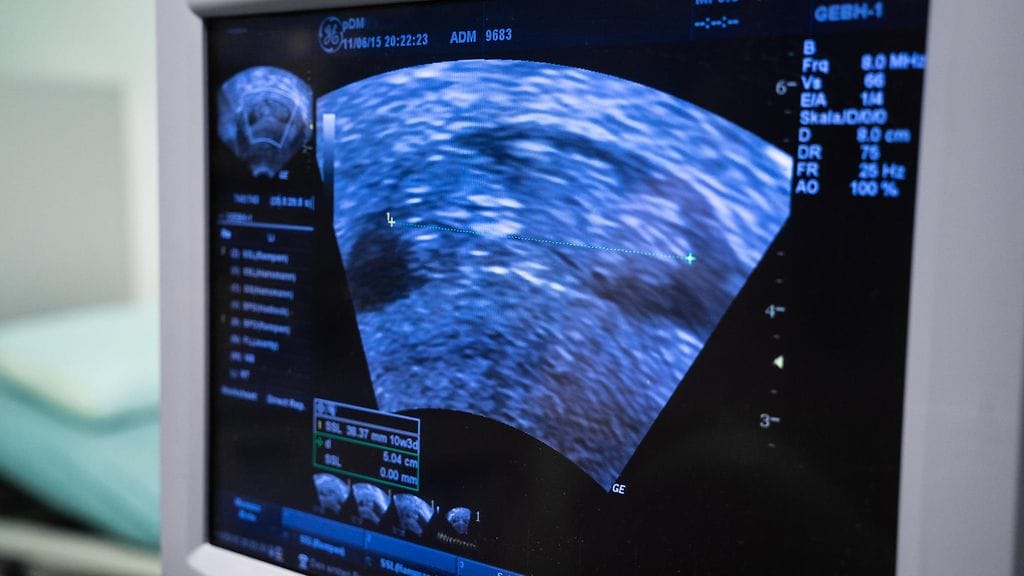

Belen Aguilera törmäsi Facebookissa lapsensa ultraäänikuvaan. Kävi ilmi, että moni äiti oli vuosien ajan saanut lääkäriltään saman kuvan "omasta lapsestaan".

Belen Aguilera selasi Facebookia, kun hän tajusi tulleensa huijatuksi. Chilessä asuva Belen selaili julkaisuja, kun hän törmäsi tutun oloiseen ultraäänikuvaan. Vuosia sitten hän oli saanut saman ultrakuvan tyttärestään.

– Ne ovat samanlaisia, samat yksityiskohdat, kaikki. Toinen vauva oli päivämäärämerkitty kuuden vuoden taakse, minun tyttäreni on vuoden ja 10 kuukautta, Belen ihmetteli Facebookissa.